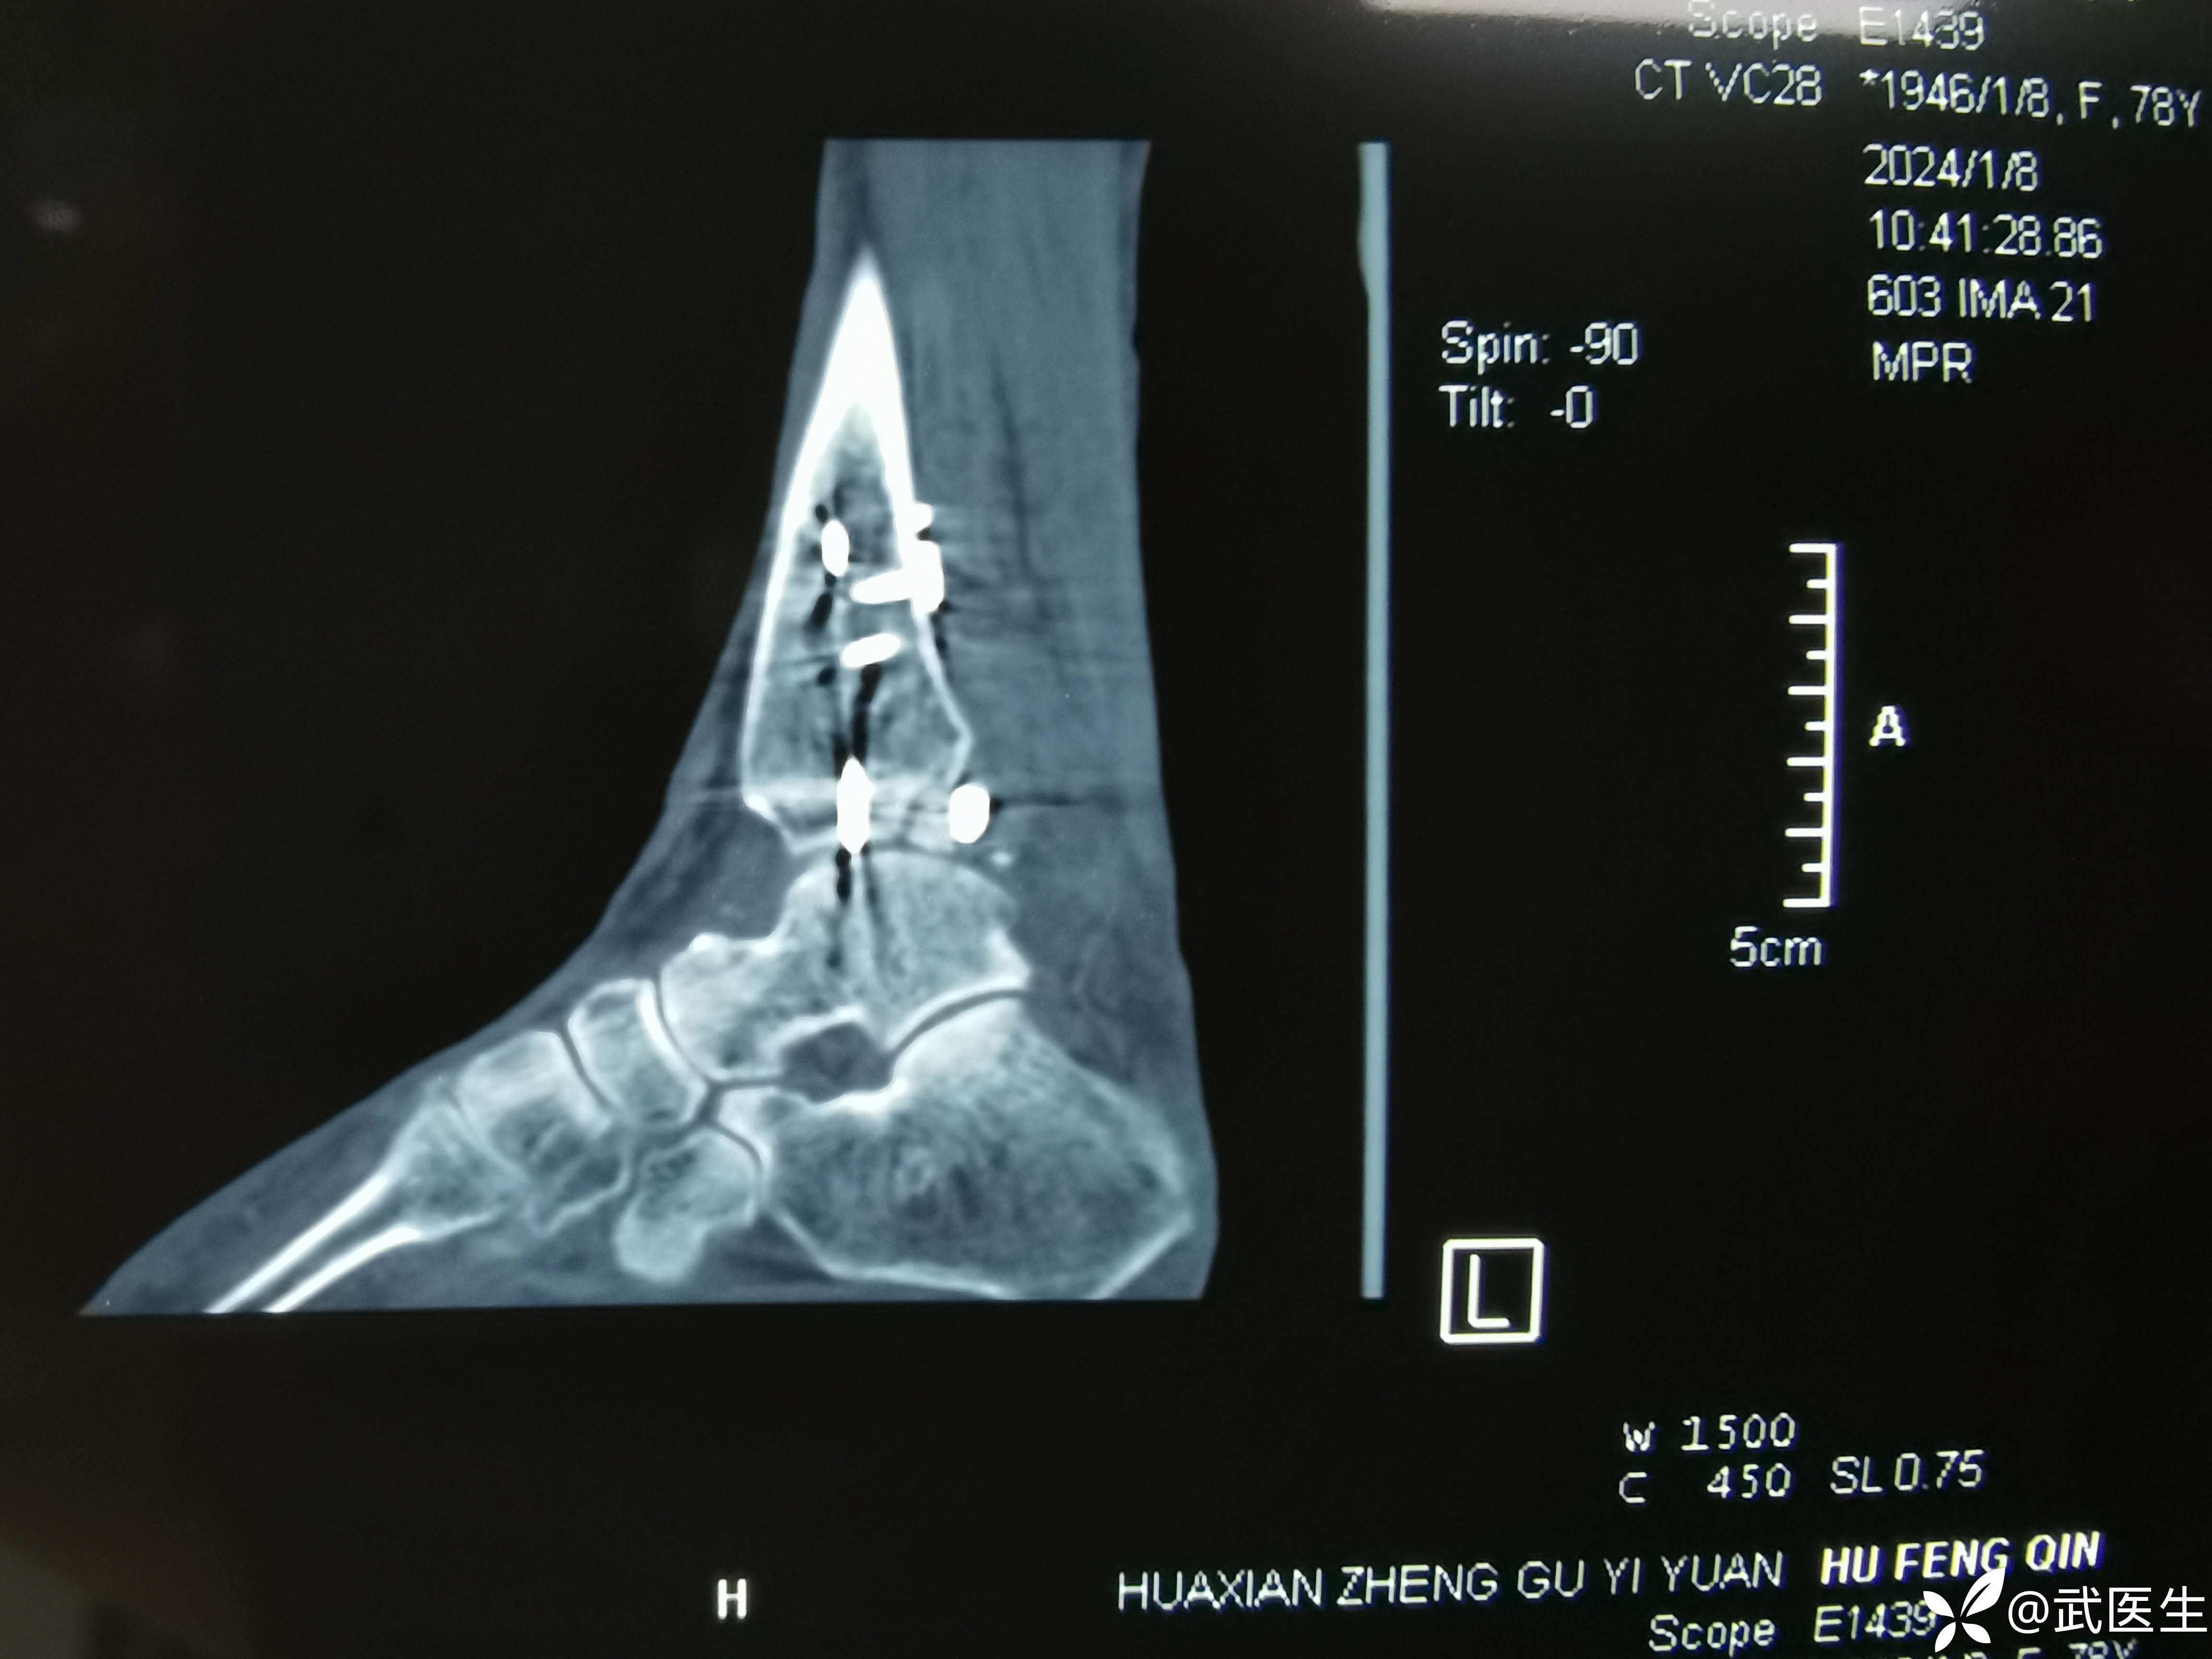

术后ct,复位还行